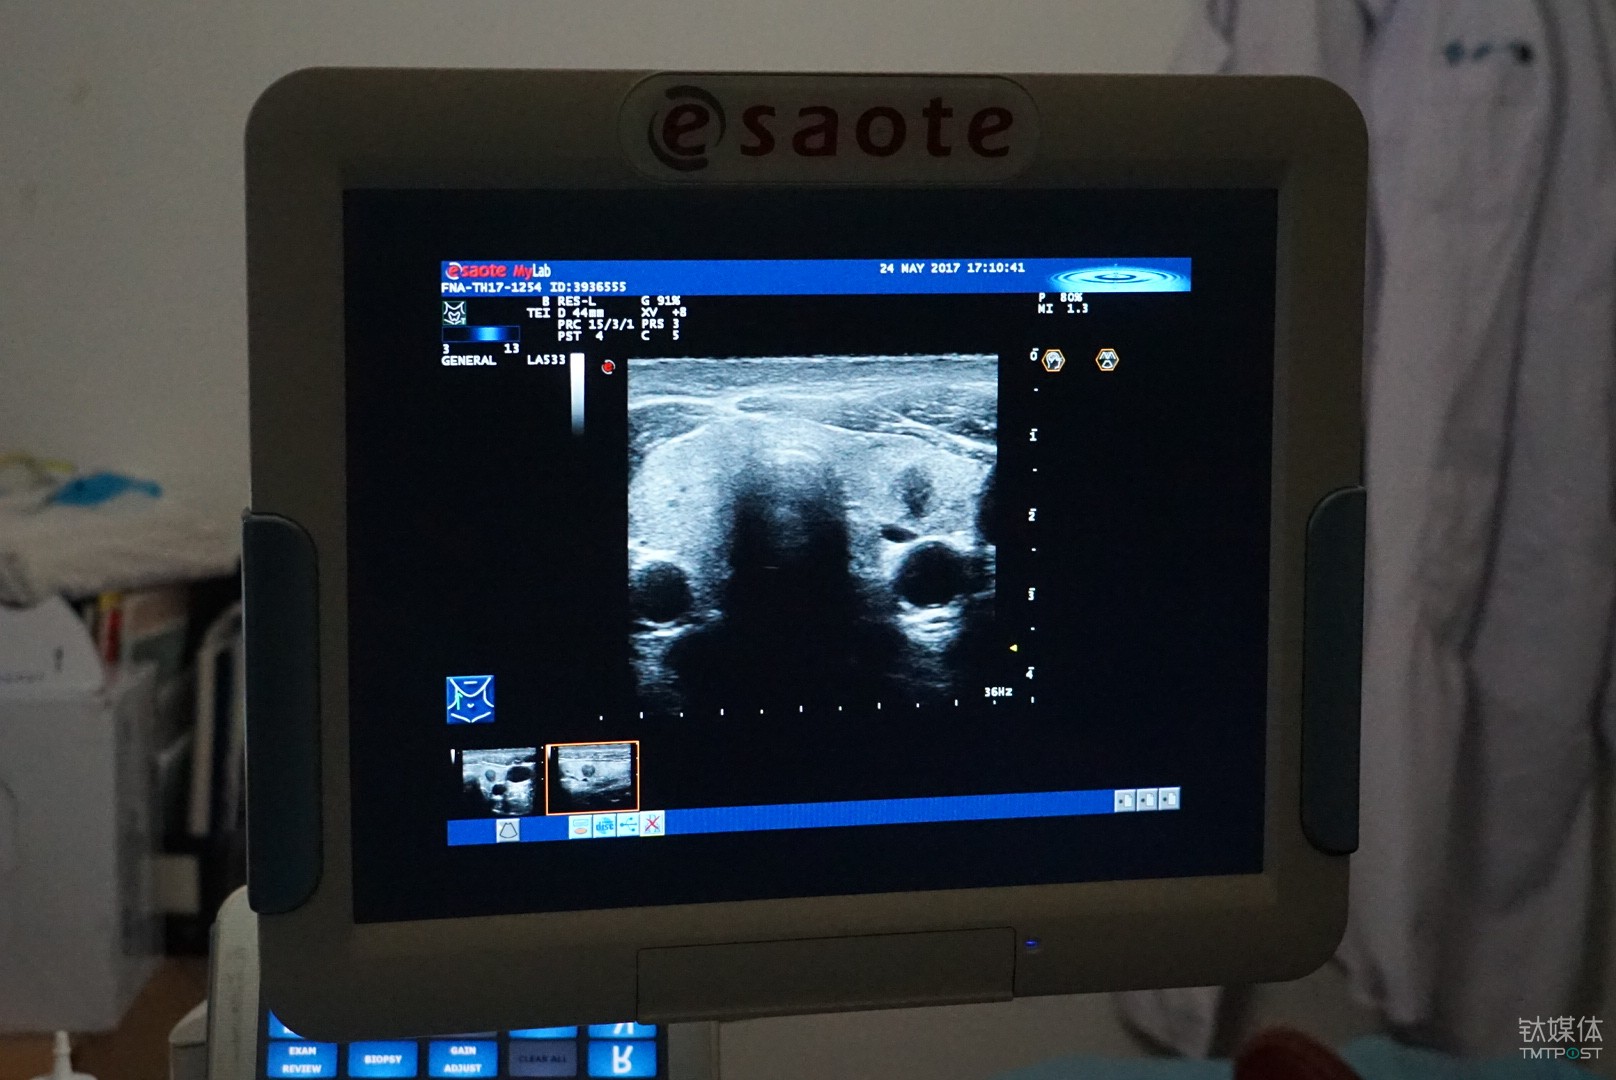

類似的案例也出現(xiàn)在了浙江大學(xué)附屬第一學(xué)院的超聲醫(yī)學(xué)科,該病院是率先嘗試用人工智能方式輔助診斷甲狀腺結(jié)節(jié)的醫(yī)學(xué)機構(gòu)。

具體而言,這是一套由德尚韻興與浙江大學(xué)特聘教授孔德興團(tuán)隊主導(dǎo),依托英特爾至強融合處理器平臺開發(fā)而來的輔助診斷系統(tǒng)。

從功能上來說,這是一套基于超聲波影象的甲狀腺結(jié)節(jié)良惡性的輔助診斷系統(tǒng),按照甲狀腺結(jié)節(jié)檢查時候拍攝的醫(yī)學(xué)影像的特征,通過對圖像的識別和標(biāo)注,來幫手醫(yī)生更準(zhǔn)確的做出診斷結(jié)論。

對于甲狀腺結(jié)節(jié)的檢查目前主要依靠超聲的方式,相較于CT和核磁,超聲的好處是自制、靈活、無副作用,所以它也是目前臨床醫(yī)學(xué)使用最為廣泛的一種檢測手段,不足之處是圖像不清楚、造影比較大,它對醫(yī)生的要求就比較高。